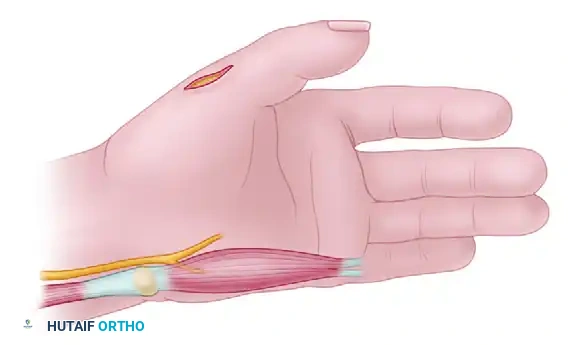

Surgical Technique 59-11: Partial Fibulectomy for Nonunion

- Positioning and Approach: Place the patient supine with a bump under the ipsilateral hip. Utilize a direct lateral approach over the palpable fibular nonunion.

- Exposure: Incise the fascia and carefully retract the peroneus longus and brevis anteriorly, protecting the superficial peroneal nerve.

- Resection: Open the fibula directly at the nonunion site. Using an oscillating saw, resect 2.0 to 2.5 cm of bone from the fibular shaft, ensuring the cuts are made in healthy, bleeding bone.

- Decompression: Perform a prophylactic lateral compartment fasciotomy if significant postoperative swelling is anticipated.

- Closure: Irrigate copiously and close the wound in a routine, layered fashion.

Postoperative Care:

Ankle and knee range of motion (ROM) exercises are initiated immediately post-surgery. Ambulation is permitted, and full weight-bearing is strongly encouraged in a short-leg, prefabricated walking boot to stimulate adjacent tibial hypertrophy and maintain functional mobility.